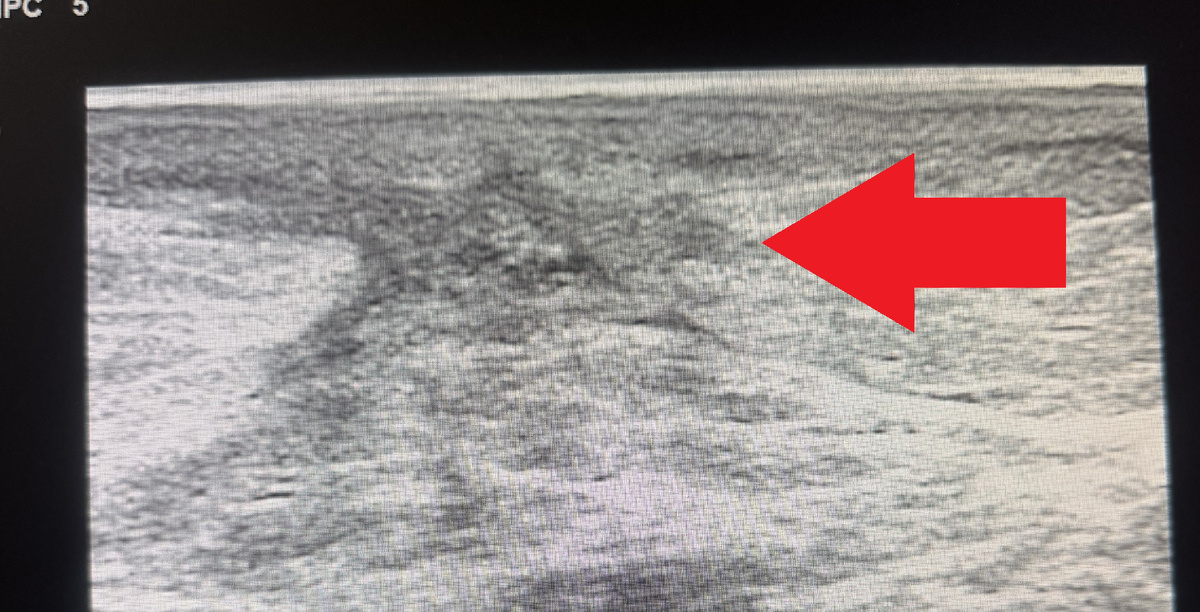

Примерно за три месяца до текущего обращения ко мне я оперировал пациентку по поводу рака молочной железы. Всё было в порядке, швы сняты, пациентка отправлена под динамическое наблюдение с контрольным обследованием через три месяца. Каково же было мое удивление, когда через три месяца после операции по данным маммографии в ткани молочной железы в зоне послеоперационного рубца была выявлено новообразование неправильной формы, с нечетким контуром, да еще и размерами 40х21мм - BI-RADS-5. BI-RADS5 – это значит, что у врача рентгенолога, описывающего маммографию, даже сомнений не было в злокачественной природе новообразования. Такое заключение нельзя игнорировать. С другой стороны, после операции прошло всего-то три месяца, рецидив не должен был возникнуть в столь короткое время. Пальпаторно под послеоперационным рубцом определялось овальной формы безболезненное несмещаемое уплотнение. Первым делом я оценил характеристики новообразования по УЗИ – и успокоился почти полностью. По УЗИ опреде